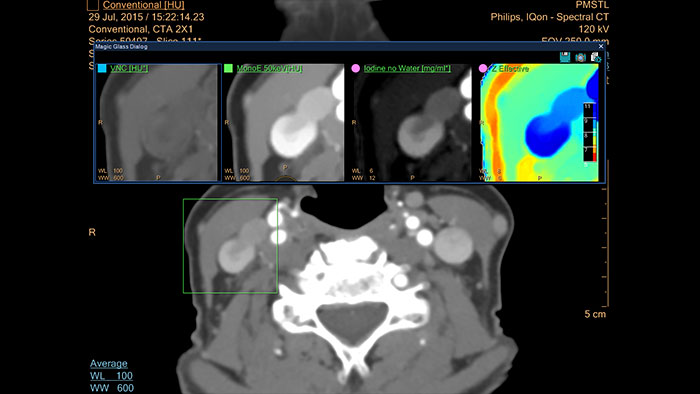

IQon Spectral CT is the only scanner to offer CT Spectral Light Magic Glass and CT Spectral Magic Glass on PACS, helping radiologists review and analyze multiple layers of spectral data at once, including on their PACS.

The spectral viewer is optimized for analysis of spectral data sets from the IQon Spectral CT Scanner. Obtain a comprehensive overview of each patient quickly and easily, quantify quickly, and assist in diagnosis. It is designed to accommodate general spectral viewing needs with additional tools to assist in CT images analysis.